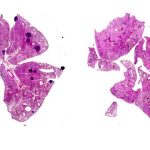

L’ articolo del New England Journal of Medicine ha esplorato l’uso di un farmaco chiamato Tulisokibart sia come trattamento per la malattia sia come diagnosi complementare per determinare la risposta al trattamento. Il farmaco agisce prendendo di mira TL1A, il prodotto di un gene espresso in molte diverse cellule infiammatorie.

Lo studio in doppio cieco ha coinvolto due gruppi di pazienti. Il primo era composto da 135 adulti con colite ulcerosa da moderata a grave che non avevano risposto ai trattamenti attualmente disponibili. Ai partecipanti è stato assegnato in modo casuale Tulisokibart o un placebo e sono stati seguiti per un periodo di 12 settimane. Lo studio ha rilevato che una percentuale significativamente più alta di partecipanti che hanno ricevuto il trattamento (26%) ha avuto una remissione clinica rispetto al placebo (1%).

Non tutti i pazienti con colite ulcerosa hanno il gene per TL1A e i ricercatori hanno ipotizzato che quelli che lo hanno avrebbero risposto meglio al Tulisokibart. Per testare questa ipotesi, il secondo gruppo era composto da 43 persone, tutte con questo gene.

Questo gruppo è stato sottoposto agli stessi protocolli del primo. In entrambi i gruppi, i ricercatori hanno scoperto che gli individui che esprimevano il gene avevano un tasso di remissione più alto (32%) rispetto al placebo (11%). Sebbene la differenza in questo gruppo esplorativo non fosse statisticamente significativa, era una prova sufficiente a supportare la fase successiva dello sviluppo di questa terapia.

Lo studio ha valutato l’efficacia e la sicurezza del Guselkumab come trattamento per la colite ulcerosa moderatamente o gravemente attiva. Lo studio in doppio cieco ha seguito 701 pazienti nel corso di 44 settimane e li ha randomizzati a Guselkumab o a un placebo.

I ricercatori hanno scoperto che coloro che assumevano il farmaco avevano una remissione clinica significativamente maggiore (23%) rispetto a coloro che ricevevano placebo (8%) a 12 settimane ed erano più propensi a mantenere la remissione a 44 settimane (50% contro 19%). Hanno anche scoperto che la sicurezza complessiva del farmaco era favorevole e coerente con quella riscontrata nelle indicazioni approvate e, più in generale, con la classe di inibitori dell’IL-23 precedentemente studiata.